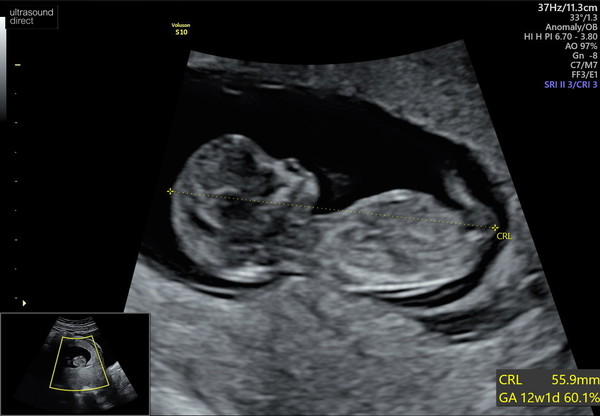

My NHS scan is not until 13+4 so I had a private scan on Thurs at 11 +7. It was so worth it 100% put my mind at ease we were both over the moon and it was amazing they had a huge TV screen on the wall directly ahead of the bed so we could watch it all and they printed about 7 pics and sent them and a little video to my mobile. They dated me at 12+1 so as I expected really and due 19th Feb. So lovely to see everyone having their scans and happy news ❤

@AprilFernLouise lovely scan photo :)